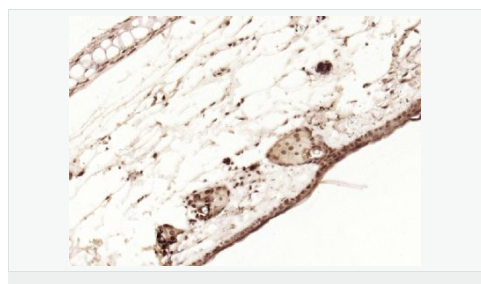

image.png